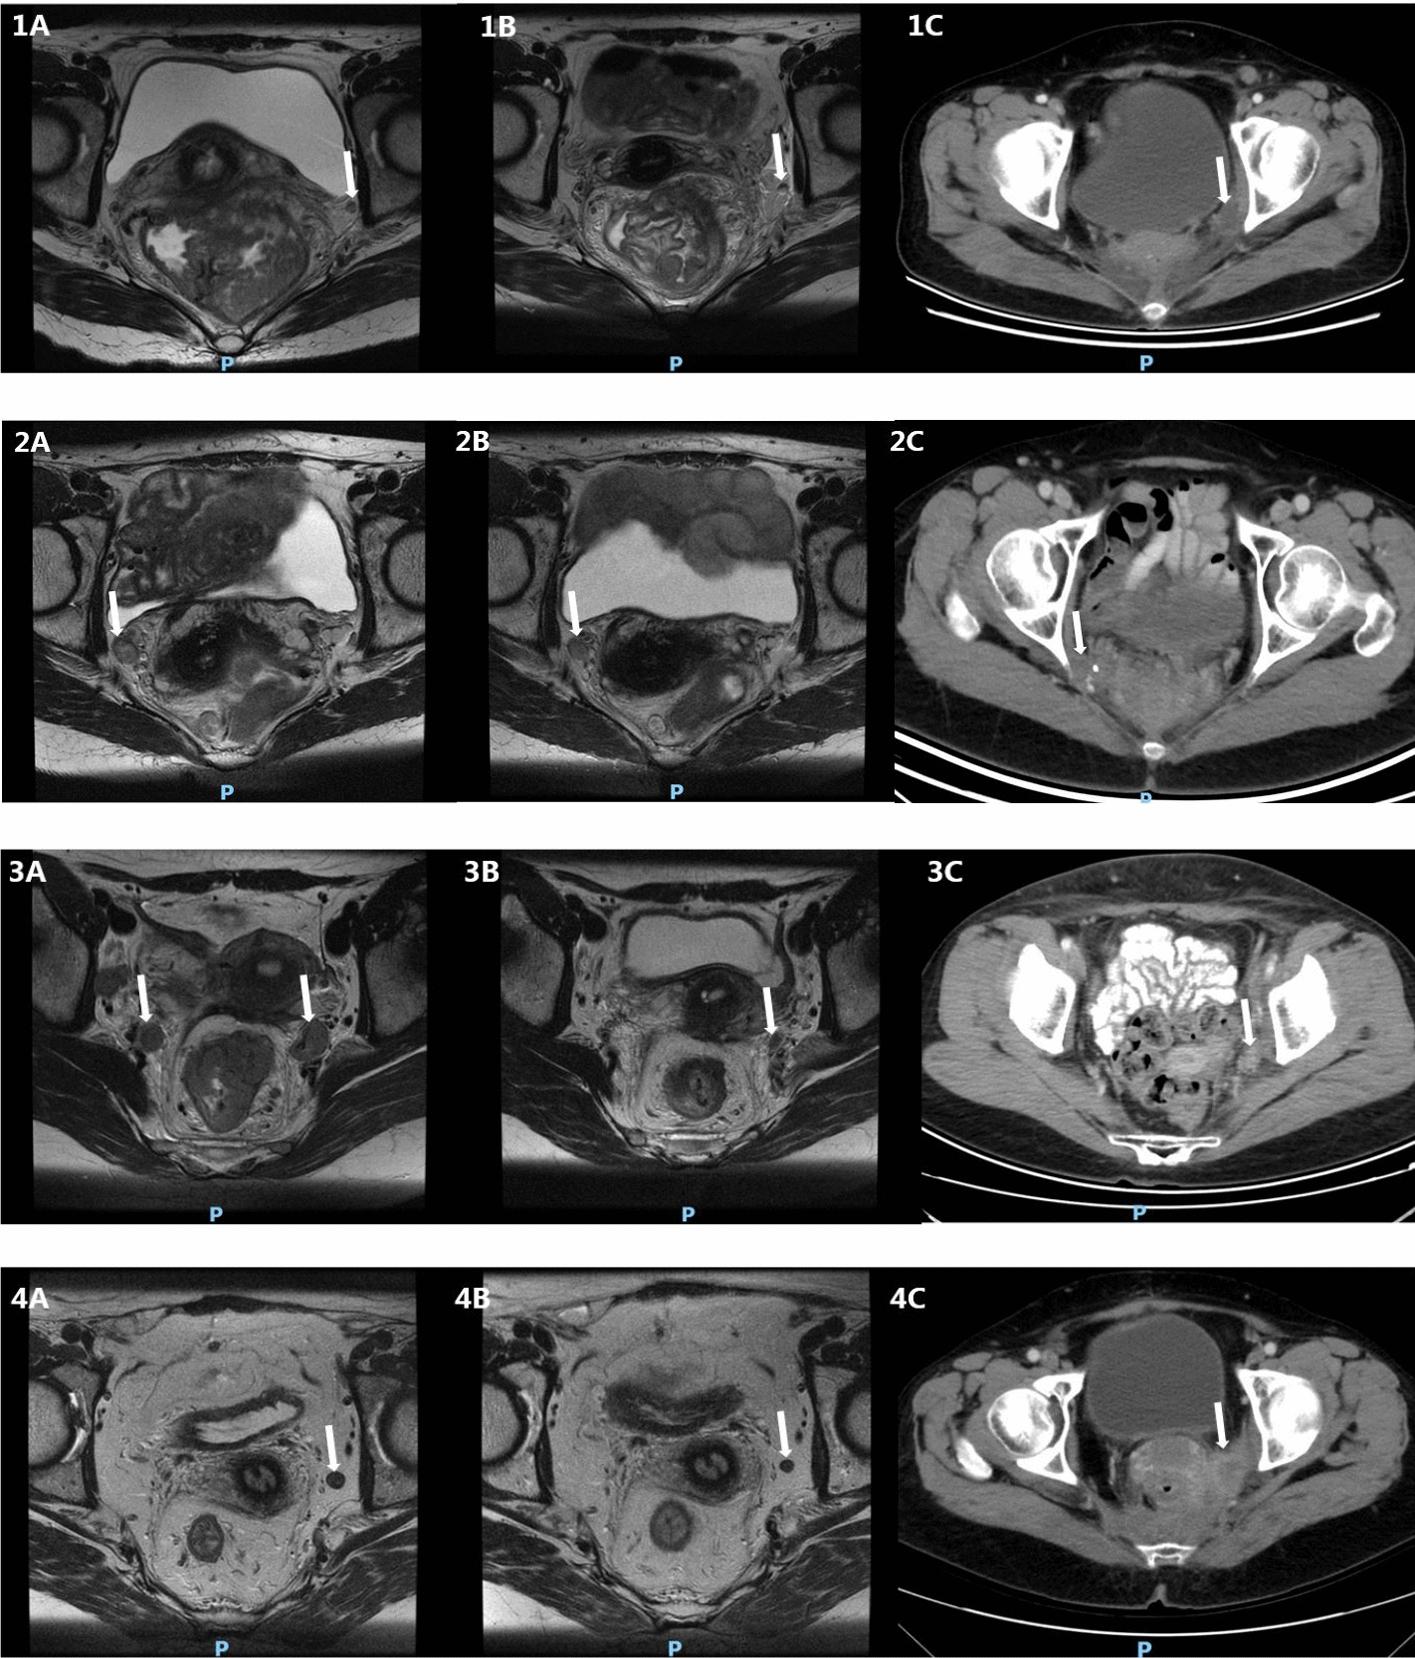

A total of 651 LARC patients were included, 160 (24.6%) of whom had positive LPLN and 491 (75.4%) had negative LPLN. Before PSM, the LPLN-positive group had higher rates of lower location (53.1% vs. 43.0%, P = 0.025), T4 stage (37.5% vs. 23.2%, P = 0.002), mesorectal fascia (MRF)-positive (53.9% vs. 35.4%, P < 0.001) and extramural venous invasion (EMVI)-positive (51.2% vs. 27.2%, P < 0.001) disease than the LPLN-negative group. After PSM, there were 114 patients for each group along with the balanced clinical factors, and both groups had comparable surgery, pathologic complete response (pCR), and ypN stage rates. The median follow-up was 45.9 months, 3-year OS (88.3% vs. 92.1%, P = 0.276) and LRR (5.7% vs. 2.8%, P = 0.172) rates were comparable between LPLN-positive and LPLN-negative groups. Meanwhile, despite no statistical difference, 3-year PFS (78.8% vs. 85.9%, P = 0.065) and DM (20.4% vs. 13.3%, P = 0.061) rates slightly differed between the groups. 45 patients were diagnosed with DM, 11 (39.3%) LPLN-positive and 3 (17.6%) LPLN-negative patients were diagnosed with oligometastases (P = 0.109).

共纳入651例LARC患者,其中160例(24.6%)LPLN阳性,491例(75.4%)LPLN阴性。PSM前,LPLN阳性组低位病变(53.1%对43.0%,P = 0.025)、T4期(37.5%对23.2%,P = 0.002)、直肠系膜筋膜(MRF)阳性(53.9%对35.4%,P < 0.001)及壁外静脉侵犯(EMVI)阳性(51.2%对27.2%,P < 0.001)疾病的发生率高于LPLN阴性组。PSM后,每组各有114例患者且临床因素得到平衡,两组在手术、病理完全缓解(pCR)及ypN分期率方面具有可比性。中位随访时间为45.9个月,LPLN阳性组与LPLN阴性组的3年总生存率(88.3%对92.1%,P = 0.276)和局部区域复发率(5.7%对2.8%,P = 0.172)具有可比性。同时,尽管无统计学差异,但两组的3年无进展生存率(78.8%对85.9%,P = 0.065)和远处转移率(20.4%对13.3%,P = 0.061)略有不同。45例患者被诊断为远处转移,11例(39.3%)LPLN阳性患者和3例(17.6%)LPLN阴性患者被诊断为寡转移(P = 0.109)。